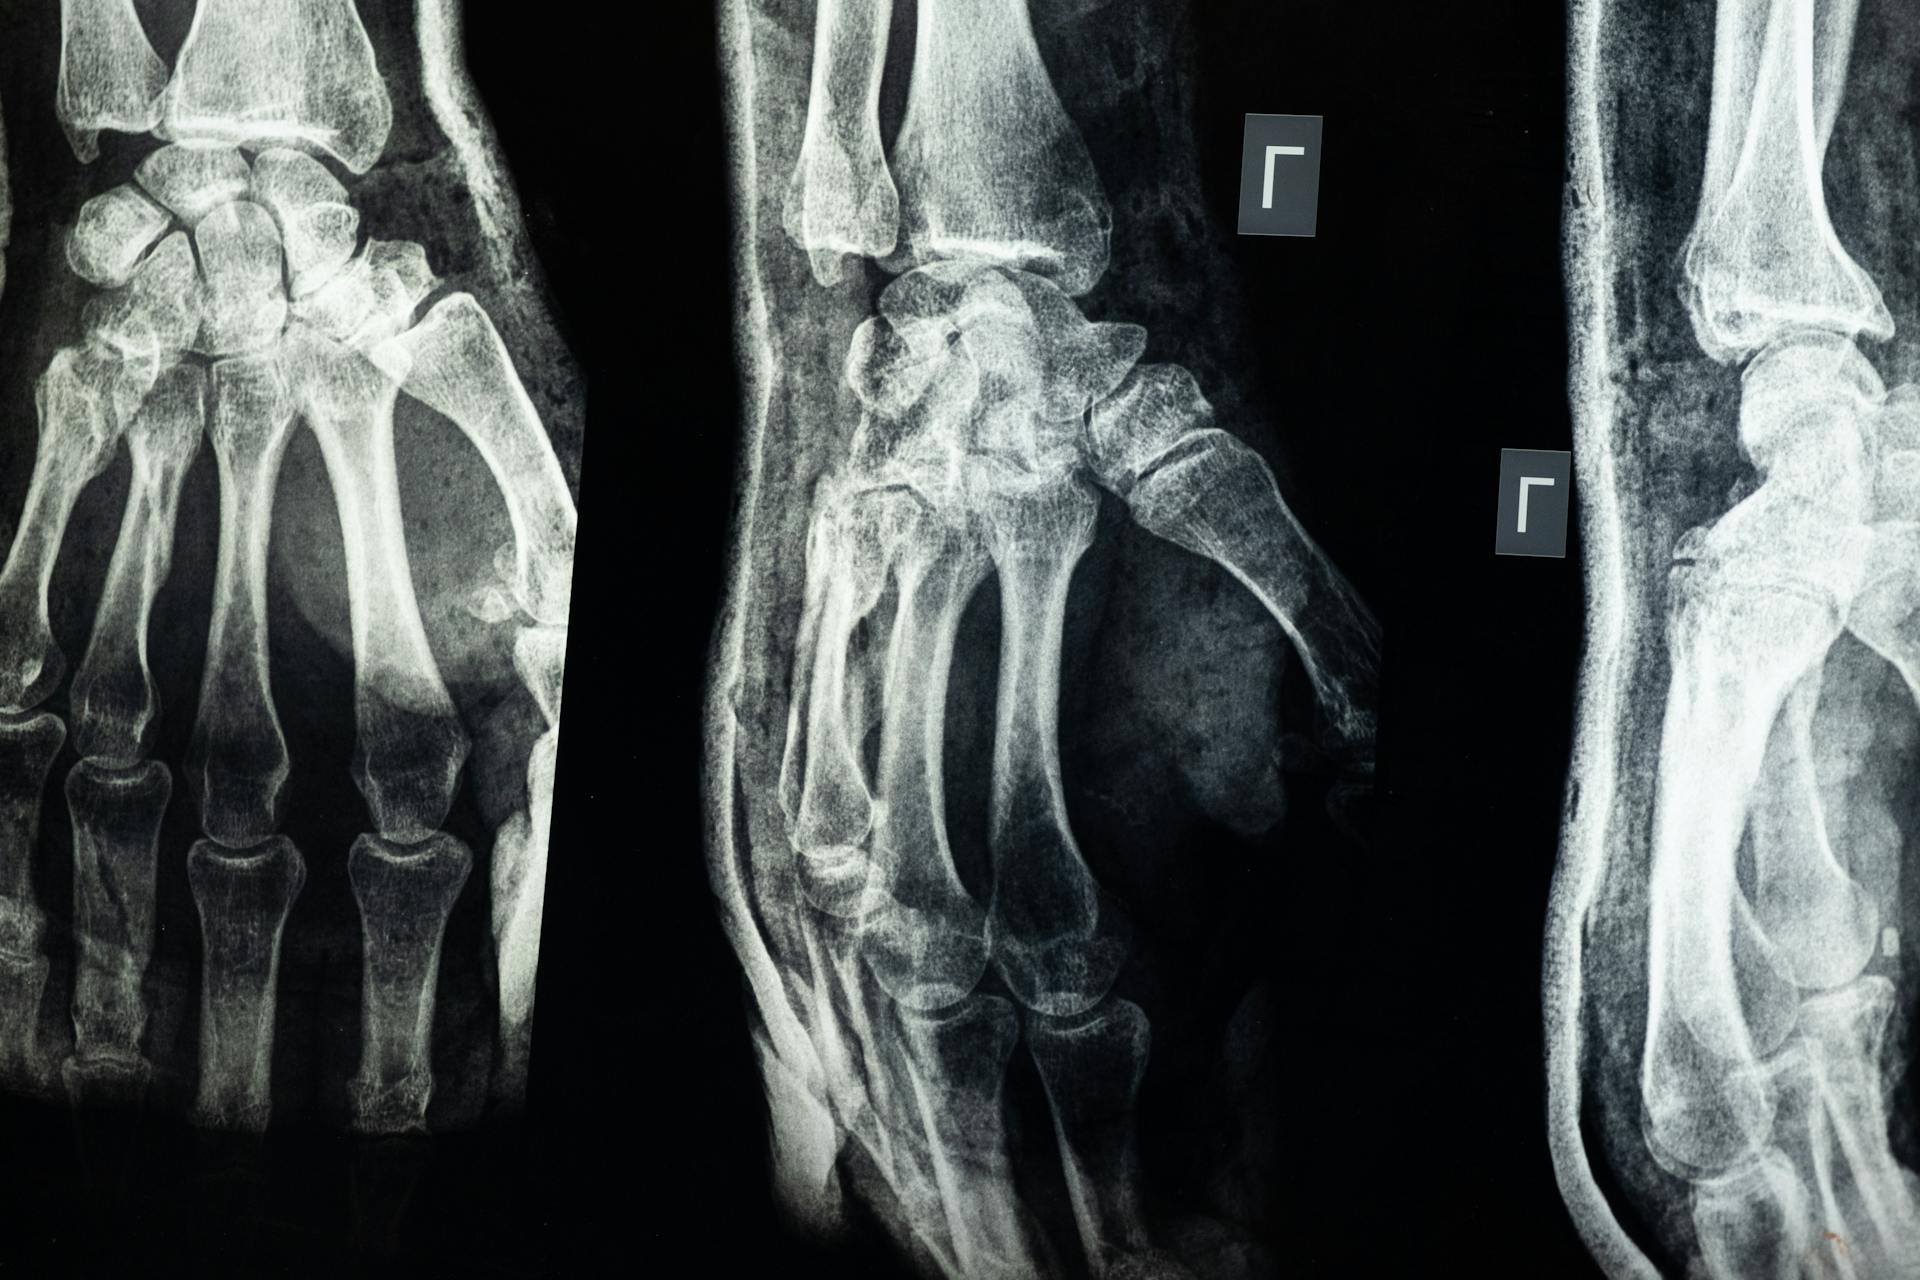

W Polsce można wykonać RTG bez skierowania wyłącznie w obszarze stomatologicznym, natomiast pozostałe rodzaje badań RTG wymagają skierowania na RTG z uwagi na regulacje dotyczące ochrony radiologicznej. Oznacza to, że zdjęcia klatki piersiowej, jamy brzusznej czy kręgosłupa są wykonywane wyłącznie po ocenie lekarza.

RTG punktowe pozwala ocenić pojedyncze zęby, co jest przydatne przy wykrywaniu próchnicy lub stanów zapalnych miazgi. Pantomogram umożliwia ogląd szczęki i żuchwy, a jego wykonanie ułatwia planowanie leczenia ogólnego. Badania te są często zalecane przed leczeniem w gabinecie stomatologicznym.

Badania radiologiczne klatki piersiowej, jamy brzusznej czy kręgosłupa generują wyższą dawkę promieniowania, dlatego ocena wskazań medycznych jest kluczowa. Dane naukowe wskazują, że promieniowanie powinno być ograniczane do sytuacji diagnostycznie koniecznych.